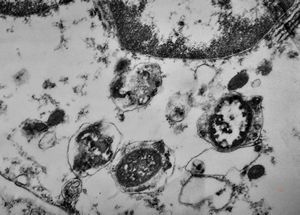

F,50y. | progressive multifocal leukoencephalopathy- viral particles in a glial cell

F,50y. | progressive multifocal leukoencephalopathy- viral particles in a glial cell

F,50y. | progressive multifocal leukoencephalopathy- viral particles in a glial cell